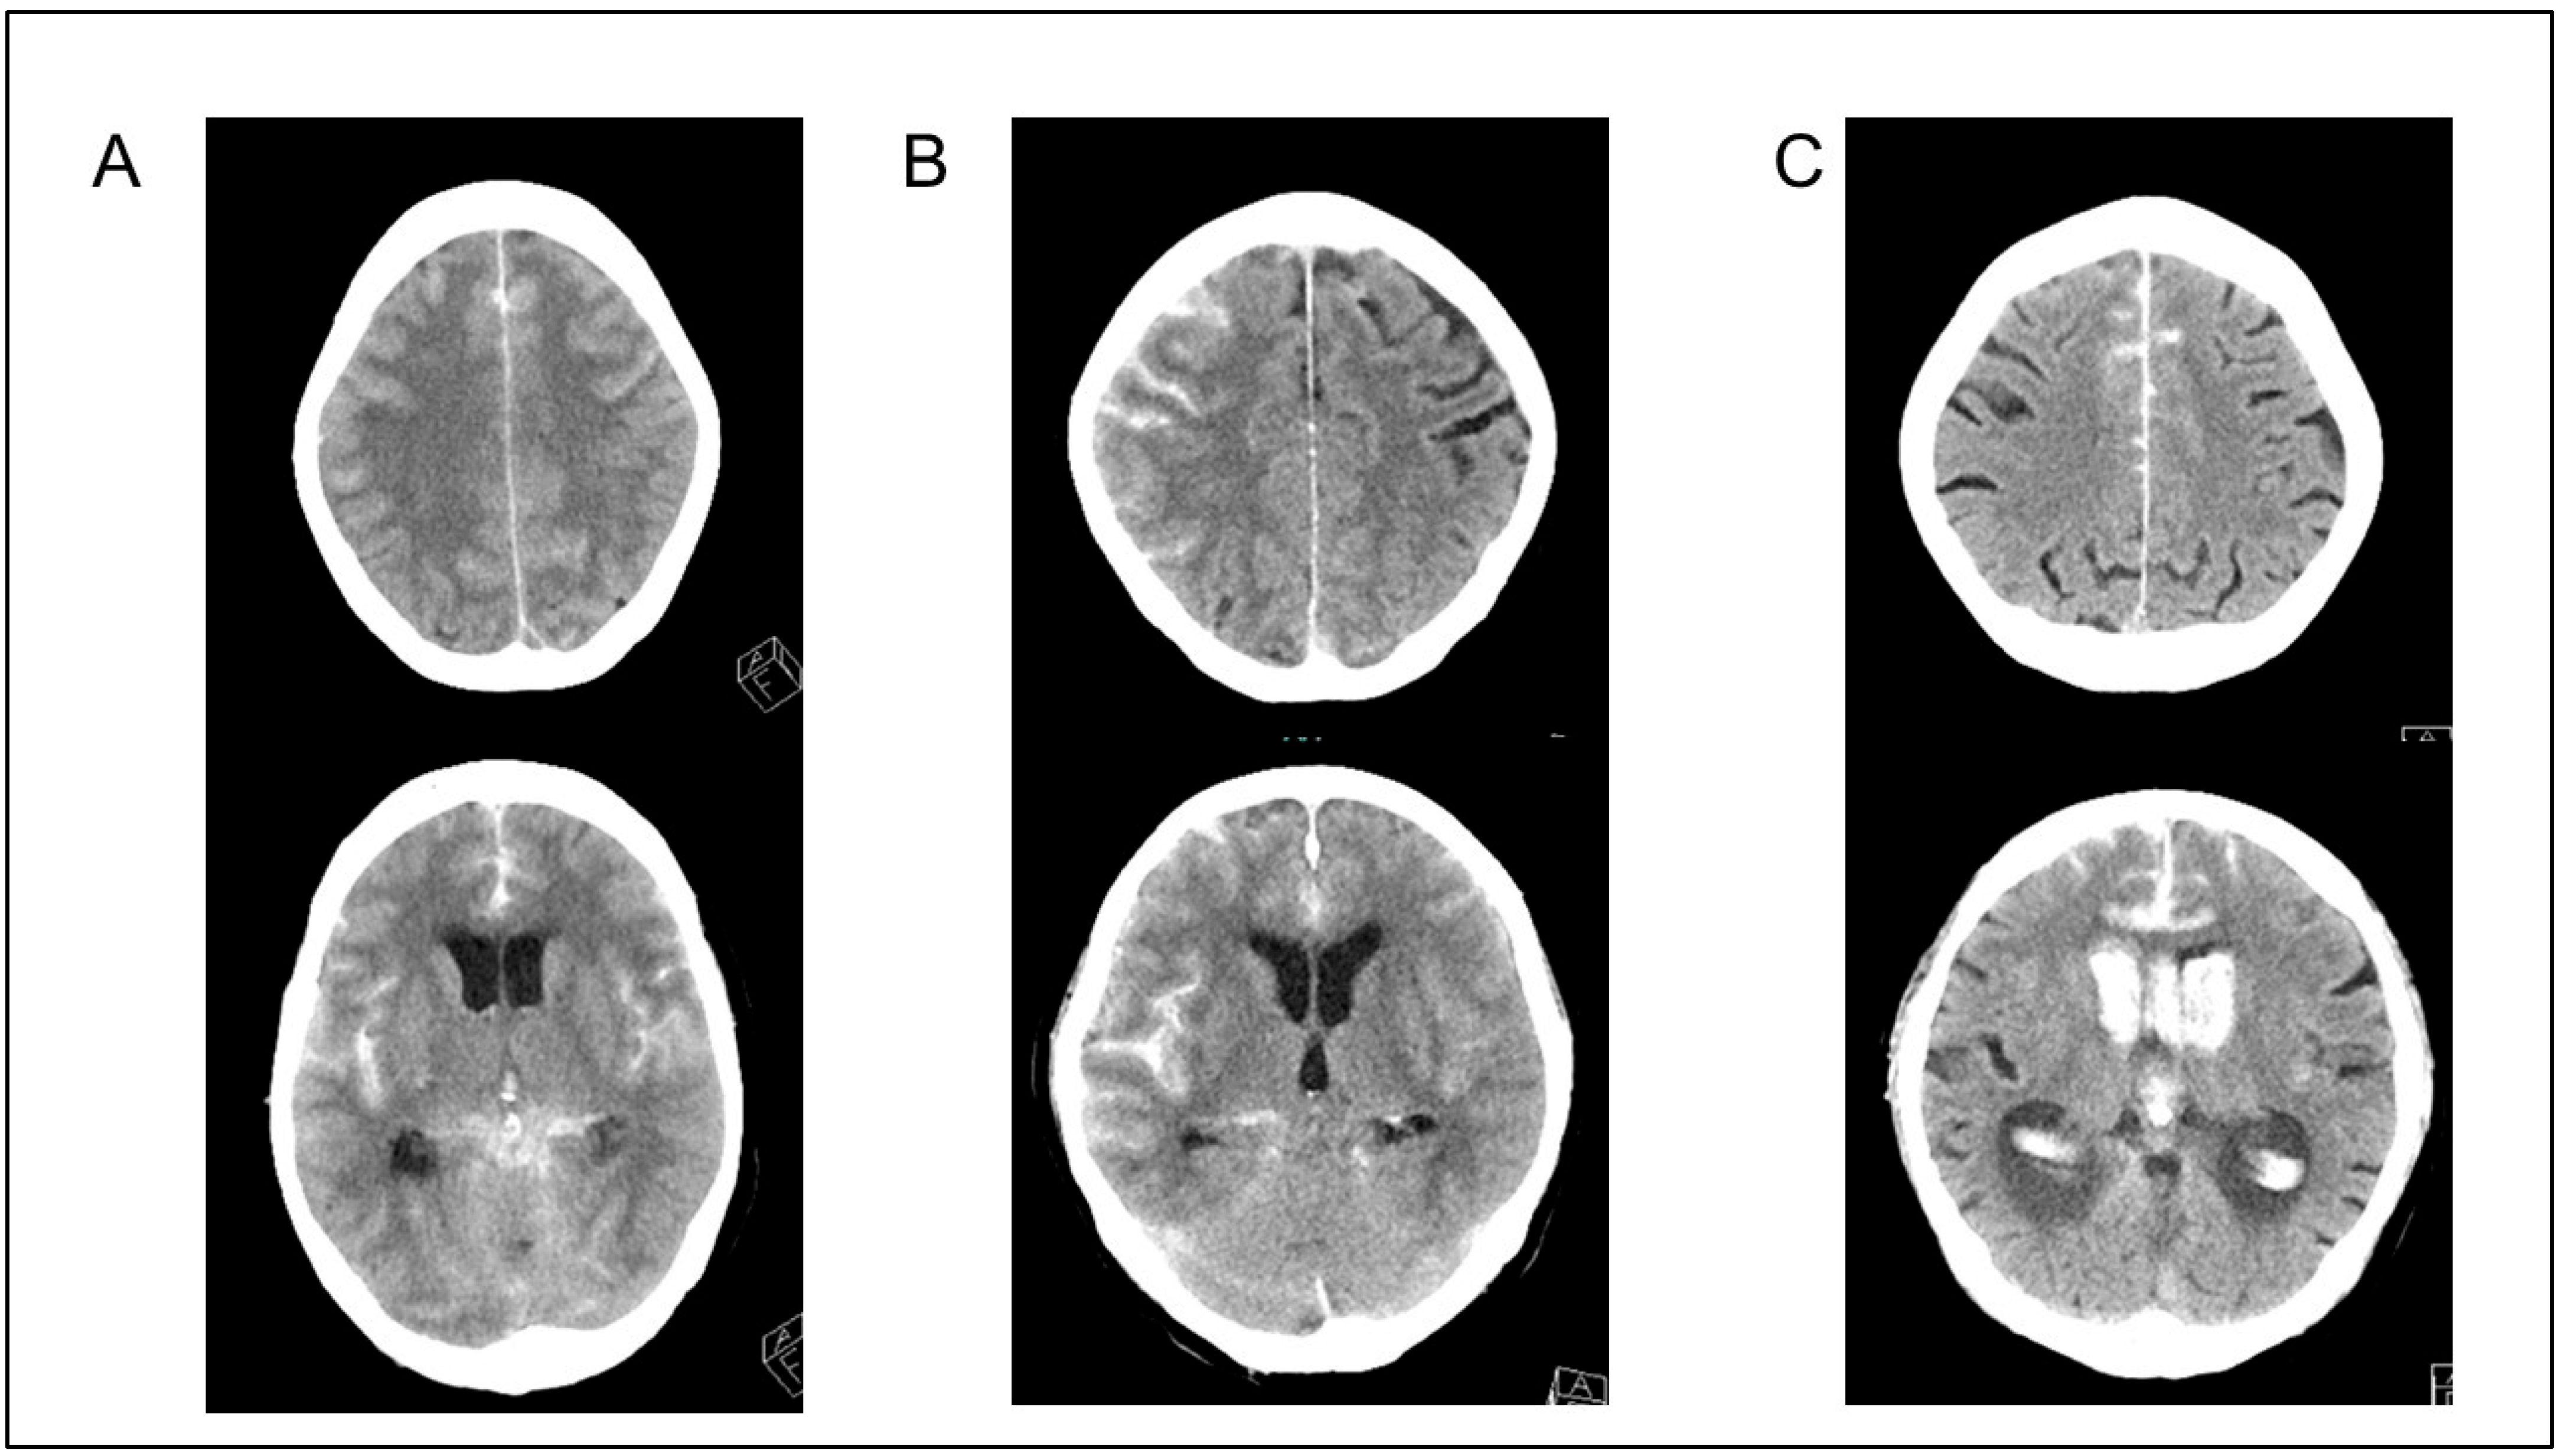

2.4. Clinical and Radiographic Assessment

3.4. DCI Occurrence in Patients with Both GCE and Infection